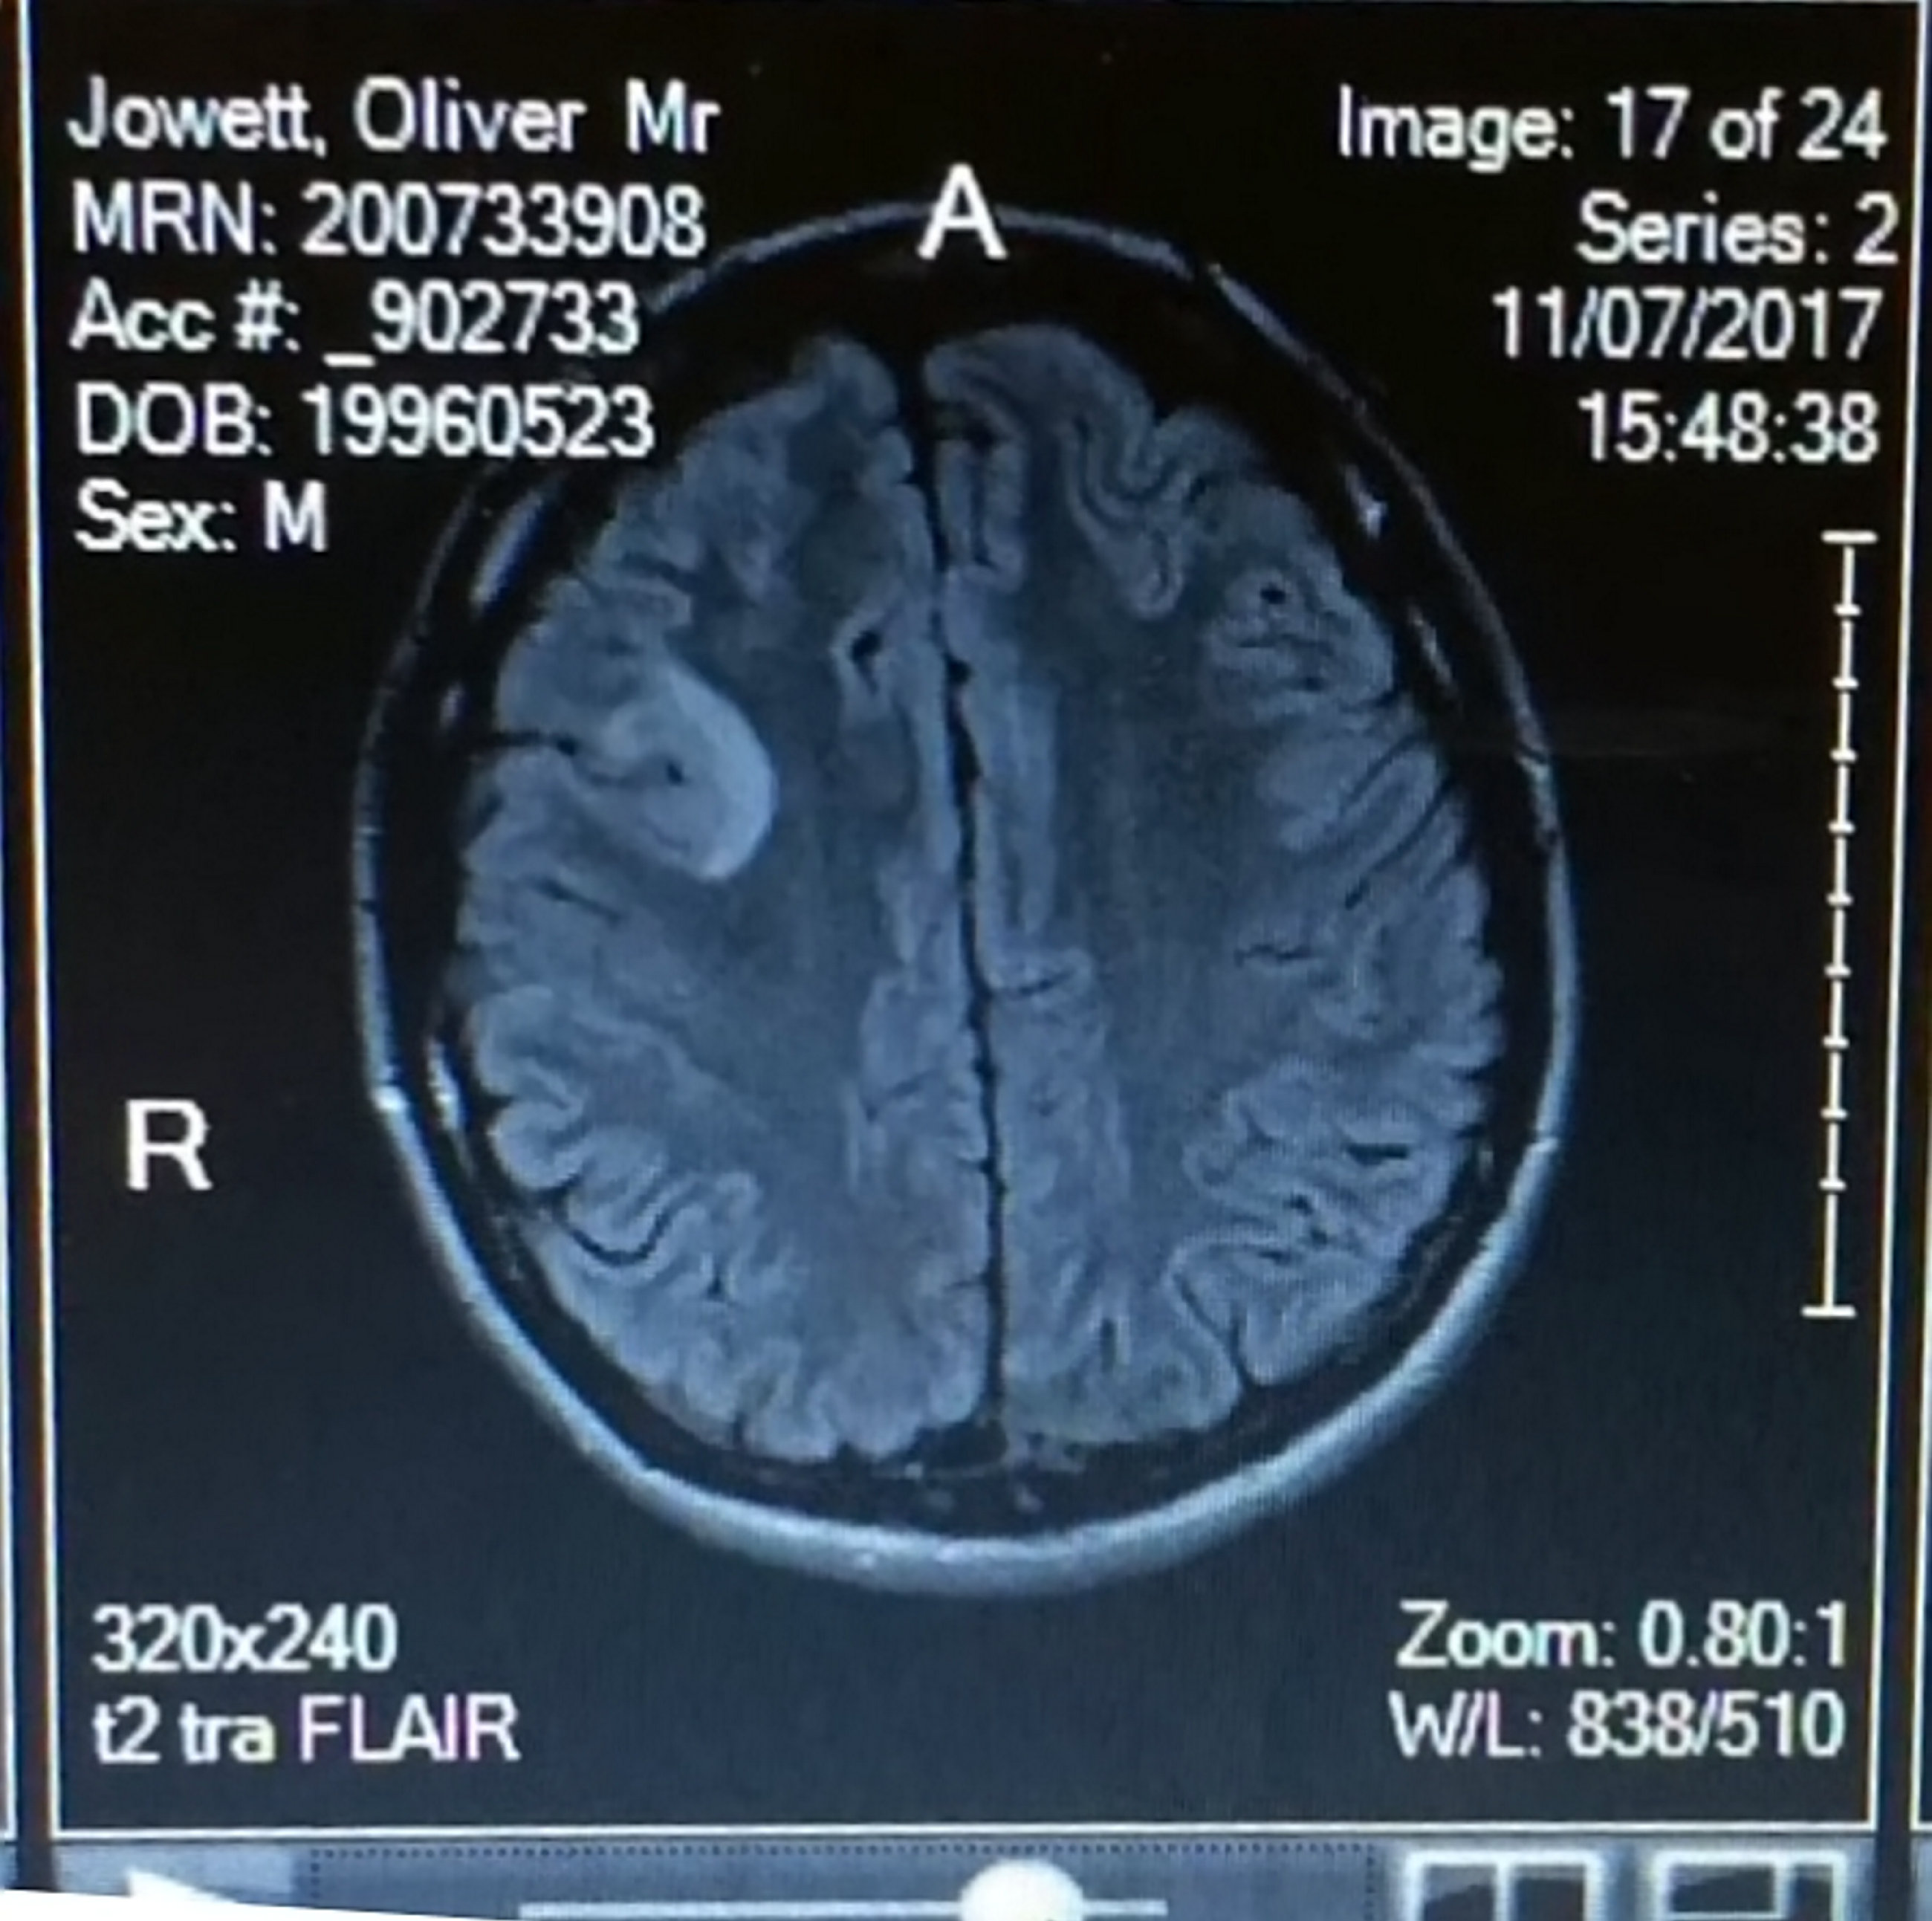

▼來自英國的歐利(Ollie Jowett)年僅22歲,他在2017年9月被確診出罹患了惡性腦瘤,醫生預估他只剩下5年的壽命。